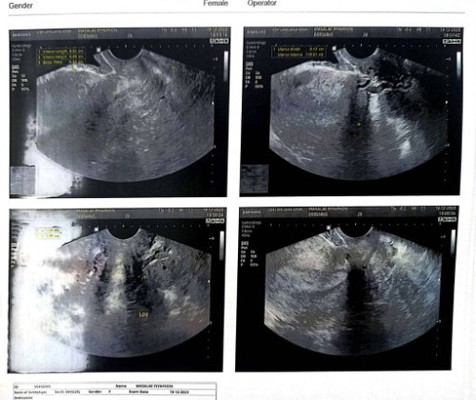

ซาวด์แล้วไม่เจอถุงตั้งครรภ์

อาจารย์หมอคำนวณให้อายุครรภ์ประมาณ 5w4d เช้าเมื่อวานมีเลือดออก ตรวจค่าHCG ยังท้องอยู่ แต่ซาวด์แล้วหาถุงการตั้งครรภ์ไม่เจอ กังวลมากค่ะ ใครเคยเป็นแบบนี้บ้างไม๊คะ

ถ้า ซาวน์ทางหน้าท้อง 5 w อาจจะเห็นได้ไม่ชัด ต้องซาวน์ทางช่องคลอด จะเจอถุงตั้งครรภ์ ... แนะนำไปซาวน์อีกทีช่วง 7-8 w น่า